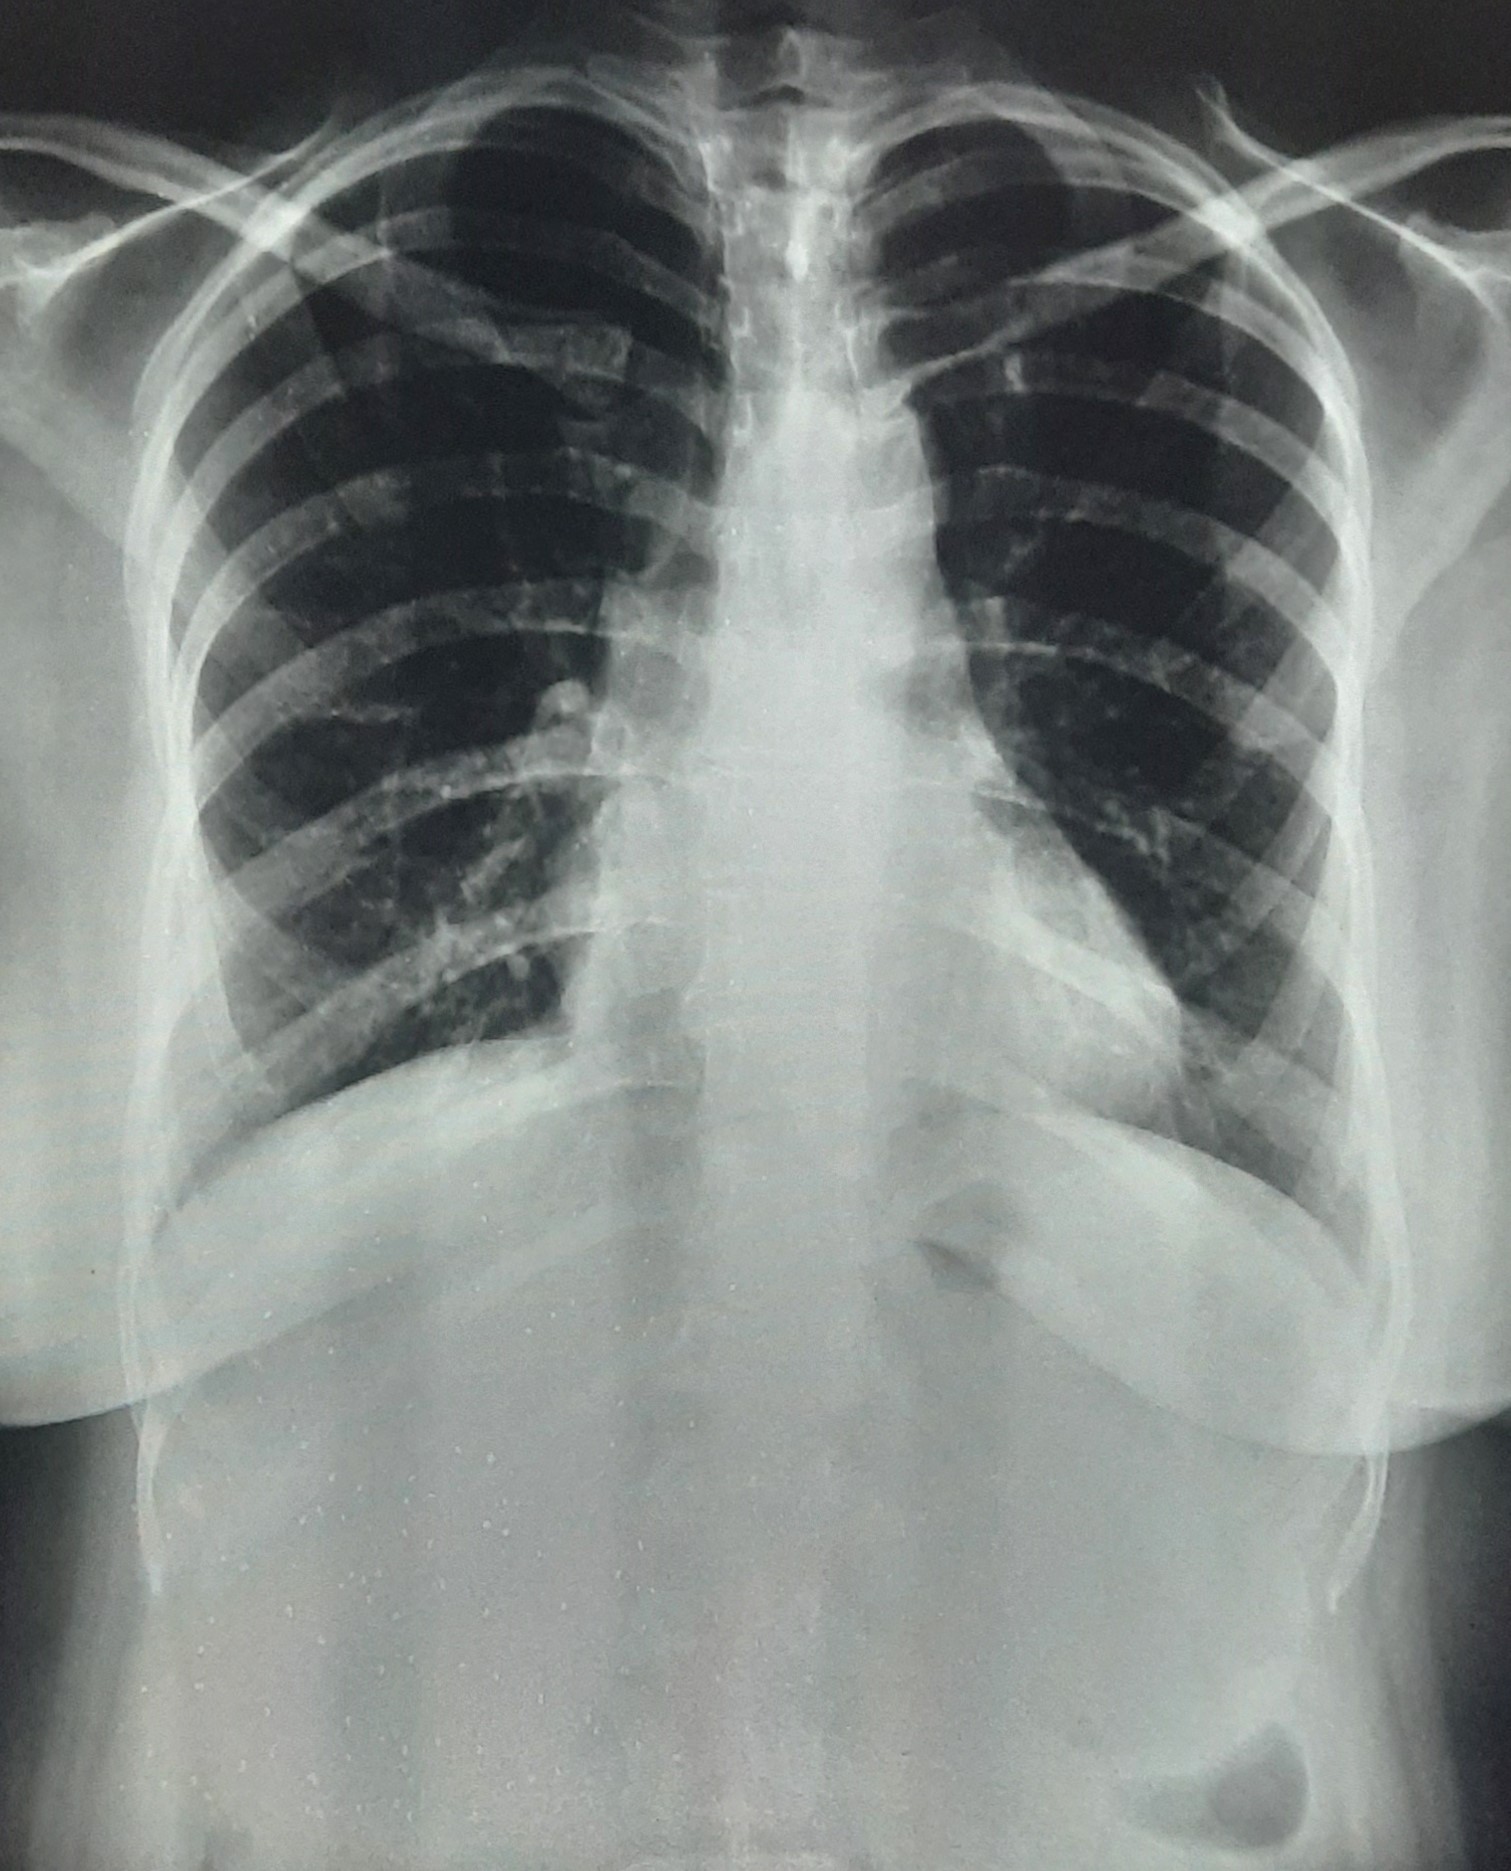

| 297 | IGGMC, Nagpur, Nagpur | P2 | 29-4175 | Sabina Parveen | Consent taken on Paper | 23 Yrs. |

Provisional Diag : PTB Reactivation

Final Diag : ? |

TB Case (Confirmed) | Bilateral Middle Lower Zone Pulmonary TB | Abnormality visible on x-ray |